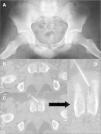

El estudio radiológico simple de abdomen, pelvis (fig. 1A) y cadera izquierda no encontró lesiones óseas significativas.

(A) Radiografía anteroposterior de pelvis informada como normal. (B) Imágenes de la tomografía computarizada que muestra la erosión ósea, la toma de biopsia con aguja fina (C) y detalle de la misma (D) que muestra que la punción-aspiración con aguja fina se realizó del interior de la lesión.

La tomografía computarizada (TC) (fig. 1B) de la pelvis ósea centrada en el pubis, con reconstrucción coronal muestra en el extremo anteromedial del pubis izquierdo una imagen lítica, polilobulada, que erosiona la cortical, sin que exista un reborde escleroso. La lesión presenta densidad en partes blandas, aunque menor a la del músculo, excluyendo la presencia de contenido líquido o grasa. No se observan calcificaciones en su interior, ni masa de partes blandas adyacente, aunque sí existe una leve tumefacción de las partes blandas en la zona anterior de la sínfisis. El resto de las estructuras óseas no presentan imágenes patológicas.

Se tomaron varias muestras mediante punción-aspiración con aguja fina (PAAF) guiada por TC (figs. 1C y 1D) a distintos niveles de la lesión. Se obtuvo un líquido de contenido serohemático, cuyo análisis microscópico reveló la existencia de células linfoplasmocitarias y hemáticas.